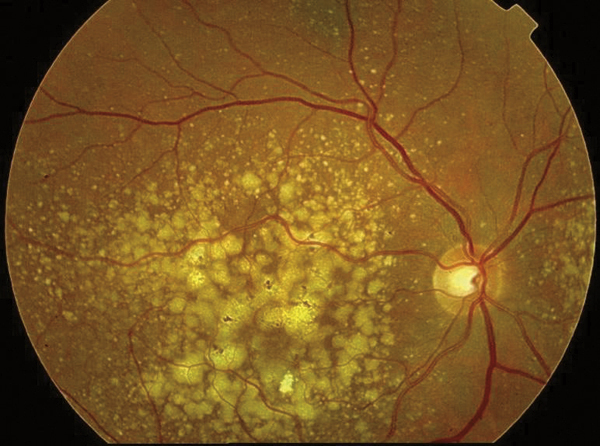

© Jean-François Korobelnik, La Revue du Praticien Nombreux grands drusen séreux dans la région maculaire.